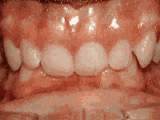

Missing lateral incisors

This patient's lateral incisors were congenitally missing. She had braces for 20 months to move the teeth into their correct positions, then the missing teeth were replaced with bonded "Maryland" bridges.